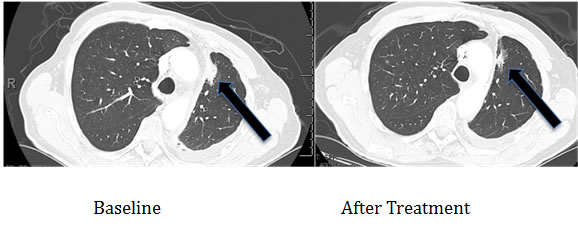

Patients

Three patients with known EGFR-(reversible TKI) resistant mutations (two with insertions in exon 20 (Table 2, Cases 1 and 2) and one with an exon 20 T790M mutation (Case 3) were treated with an EGFR antibody (cetuximab)-based regimen. Both patients with insertions in exon 20 achieved durable partial remissions consistent with the predictions from our structural modeling (Table 2, Figures 7 and 8). The third patient, having the exon 19 (LREA-type) mutation, initially responded to the reversible TKI inhibitor erlotinib (partial remission for 17 months); at the time that the T790M was detected, the patient failed to respond to erlotinib combined with cetuximab, again consistent with the molecular structure predictions.

Partial response, still progression-free at 42 months (Figure 7) |

Received cetuximab with erlotinib |

Figure 7: Computerized tomographic scan of the lungs of Patient #1 (Table 2) with EGFR aberration in exon 20 (D770>GY)) before and four months after treatment with a cetuximab-based regimen shows tumor regression.

Of interest in this regard, we report three patients treated with EGFR antibody cetuximab-based regimens (Table 2). Two of these patients had mutations considered resistant to EGFR TKI inhibitors (D770>GY and D770_P772delsinKG (both in exon 20)), yet attained partial remissions on cetuximab-based therapy (Figures 7 and 8). One patient continues to do well on treatment for over 3.5 years (Table 2, Patient #1, and Figure 7). In contrast, a patient with the exon 20 T790M EGFR-TKI resistant mutation (in addition to the exon 19 sensitive LREAdel aberration) did not respond to the combination of cetuximab and erlotinib (Table 2, Patient #3). Typically, these patients present with the sensitive EGFR LREAdel aberrations and initially respond to reversible TKIs such as erlotinib (and, a salutary effect of erlotinib was indeed seen in our patient early in the disease course), but the resistant T790M mutation then emerges [4]. Similarly Janjigian and colleagues failed to show activity for the erlotinib/cetuximab combination in patients with NSCLC and acquired resistance to erlotinib due to T790M mutations [25]. Our clinical observations are supported by the in silico modeling data (Figures 1 and 5), which demonstrate that exon 20 insertion aberrations would be expected to increase the attractive electrostatic dimerization energies, and such a change could be predicted to predispose to response to an EGFR antibody that attenuates or interferes with dimerization. Further, our modeling suggests that the LREA mutation can react to the combination of cetuximab and erlotinib, but the combination of LREA and T790M mutations can compromise this effect because of resistance of T790M mutant to TKI. Although there are limitations to this study, e.g., the small number of patients and the fact that the responders received combination therapy, the expected rate of response to the other drugs in the combination is low. These data suggest that some patients with gefitinib/erlotinib-resistant EGFR mutations, especially those in the amino acid 770 region of exon 20, may benefit from therapy with EGFR antibodies.